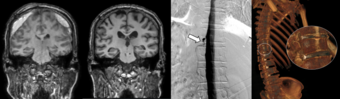

세브란스병원은 최근 DSM을 국내 최초로 도입해 이와 같은 기존 진단법의 한계를 극복했다. DSM(Digital Subtraction Myelography, 디지털 감산 척수조영술)은 척수에 조영제를 주입하고 모니터 화면으로 뇌척수액의 흐름을 실시간으로 확인할 수 있다. 이를 통해 뇌척수액이 새나가는 구멍을 정확하게 찾아낼 수 있게 됐다. DSM과 더불어 세브란스병원이 함께 진행 중인 측위 CT 척수 조영술까지, 모두 뇌척수액 정맥 누공을 진단할 수 있는 최신 기법이다.

신경과 전문의(주민경, 하우석 교수)와 신경외과 전문의(하윤 교수)가 긴밀히 협력하는 만큼 진단과 치료가 원스톱으로 가능하다. 이번에 세브란스병원을 찾은 환자들은 DSM 검사와 측위 CT 척수 조영술로 뇌척수가 새어나가는 부위를 정확히 진단 ·치료받고, 뇌압을 회복했으며 경막하출혈도 사라졌다. 이에 따라 환자들이 보였던 인지기능 저하와 보행장애도 모두 호전됐다.

하우석 교수는 “자발성 두개내압 저하증과 특별한 외상이 없이 발생하는 경막하출혈의 원인 중 하나였던 뇌척수액 척수 누공은 두통, 인지능력 저하 등 심각한 고통을 일으키지만, 기존 진단법으로는 원인 규명이 쉽지 않던 상황”이라며 “세브란스병원이 도입한 DSM과 측위 CT 척수 조영술로는 척수액 누출이 발생하는 지점을 정확히 찾아내 치료할 수 있다”고 말했다.

▲왼쪽) DSM으로 확인한 누공 위치, (오른쪽) 측위 CT 척수 조영술로 확인한 뇌척수액 정맥 누공 3D 영상.